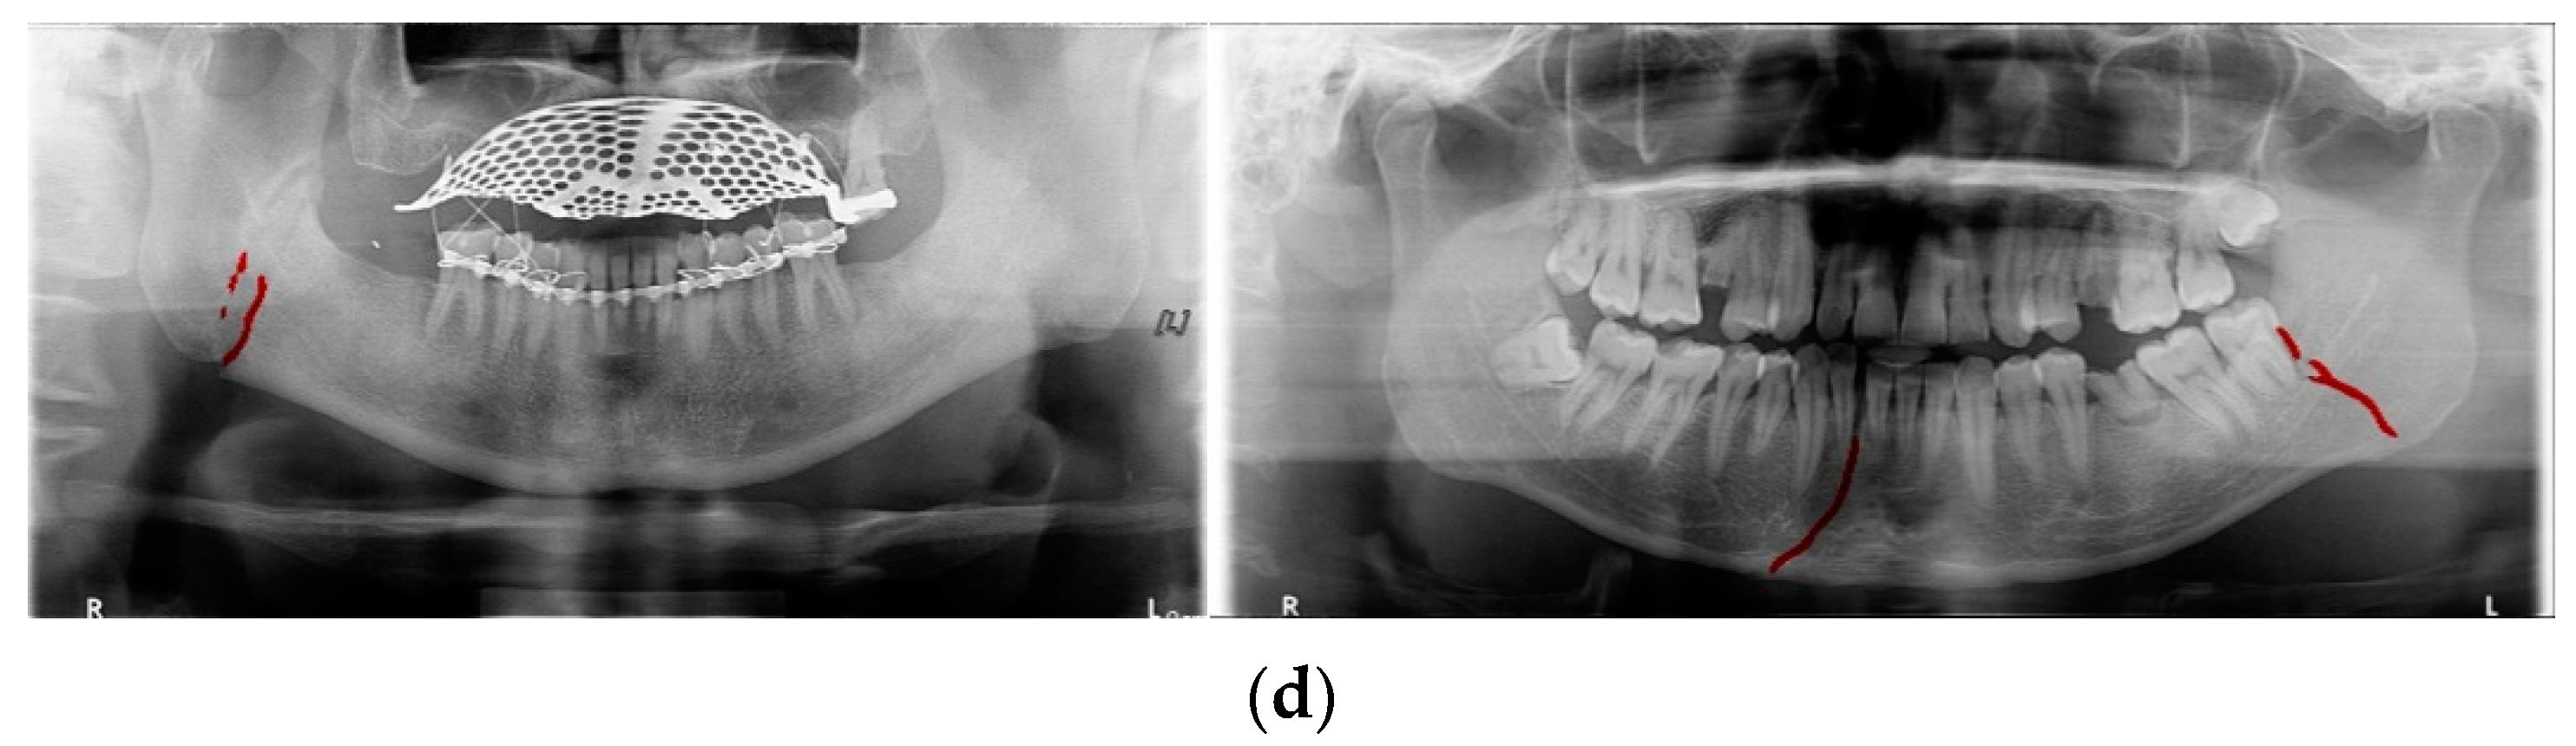

In Table 6, the parameters used for training are indicated, and in Figure 11, Figure 12 and Figure 13, the results of the doctor’s diagnosis, Mask R-CNN, YOLOv4, U-Net, LAT YOLOv4, and U-Net withYOLOv4 are compared. Figure 11 illustrates fractures in the angle and condylar regions, and in Mask R-CNN, the symphysis is misdiagnosed as a fracture. In Figure 12, the Mask R-CNN misdiagnoses the symphysis as a fracture, the result of the fact that the YOLOv4 module has better performance detecting angle fractures rather than does the LAT YOLOv4, as shown in Figure 12c,e. In short, the LAT-processed image does not always have the advantage of better revealing fractures compared with the normal panoramic radiograph.

In Figure 13, the ramus is misdiagnosed as a fracture. Therefore, Mask R-CNN had the lowest precision score because the misdiagnosis rate was higher than that of the other modules (Figure 16). The YOLO module has a low misdiagnosis rate, while the ‘undiagnosis’ rate is high; therefore, the F1 score is low owing to the ’undiagnosis’ rate. As shown in Figure 11, Figure 12 and Figure 13, YOLOv4 and LAT YOLOv4 have strong advantages over location information; therefore, they tend to detect well in the condyle region, that is, the side fracture, while they tend to detect poorly in the symphysis, body, and angle regions, where location information is ambiguous. Unlike Mask R-CNN and YOLO, U-Net is an image segmentation deep learning network, not an object detection deep learning network and labels mandibular fractures. U-Net marks fractures as lines on the label during training; however, it is difficult to label dislocated fractures, such as condyle fractures (Figure 11). Therefore, in the U-Net module, the side fracture was not diagnosed or misdiagnosed, and the precision-recall score was lower than that of the YOLO modules. It was judged that if the two deep learning networks are used together, the shortcomings of YOLO and U-Net complement each other and help improve mandibular fracture performance. In the proposed module, duplicate boxes that occurred in LAT YOLOv4 were removed before merging with the U-Net. In the proposed U-Net with LAT YOLOv4, the precision score was reduced; however, many ‘undiagnoses’ were eliminated; therefore, the recall score was increased, and it can be observed that the overall F1 score improved the performance by more than 90%.

Deep learning networks such as Mask R-CNN, YOLOv4, and U-Net have been used to detect mandibular fractures using only panoramic images. The advantages of the three networks can be identified experimentally through panoramic mandibular fracture images. First, Mask R-CNN specifically marks the fracture area; however, it also marks fractures in areas that are not fractured, such as dark shaded areas in the panoramic image or gaps between teeth; therefore, the false diagnosis rate is higher than that in other deep learning networks. In YOLO, the location information for the six classes divided into anatomical structures is helpful to detect mandibular fractures. However, there are some undiagnosed fracture areas, other than the fractures of the condyle and coronoid process with clear characteristics and location. Unlike the above two deep learning networks, U-Net performs training by labeling fracture and panoramic images. When creating training fracture labeling data, the dislocated fracture area of the condyle fracture is difficult to label. Unlike YOLO, the side fracture area is weak, causing an increase in the misdiagnosis rate when learning by labeling a dislocated fracture. In Figure 17, the mandibular fracture detection results images of LAT YOLOv4 and U-Net with LAT YOLOv4 are compared. The panoramic images in the first and second rows demonstrate the advantages of YOLO and U-Net. While YOLO detects condyle dislocation fractures well, it does not detect angle fractures; however, U-Net detects angle fractures well. The panoramic images in the third and fourth rows show that the undiagnosed area is reduced by using U-Net for the angle area that the LAT YOLOv4 module does not diagnose. Because U-Net performs semantic segmentation, it is advantageous for the segmentation of fractures spread over a wide area. Consequently, the undiagnosed case in the middle of the mandible, where LAT YOLOv4 is weak, is somewhat supplemented by the U-Net module.

Figure 17.